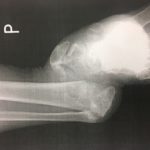

rtg przed